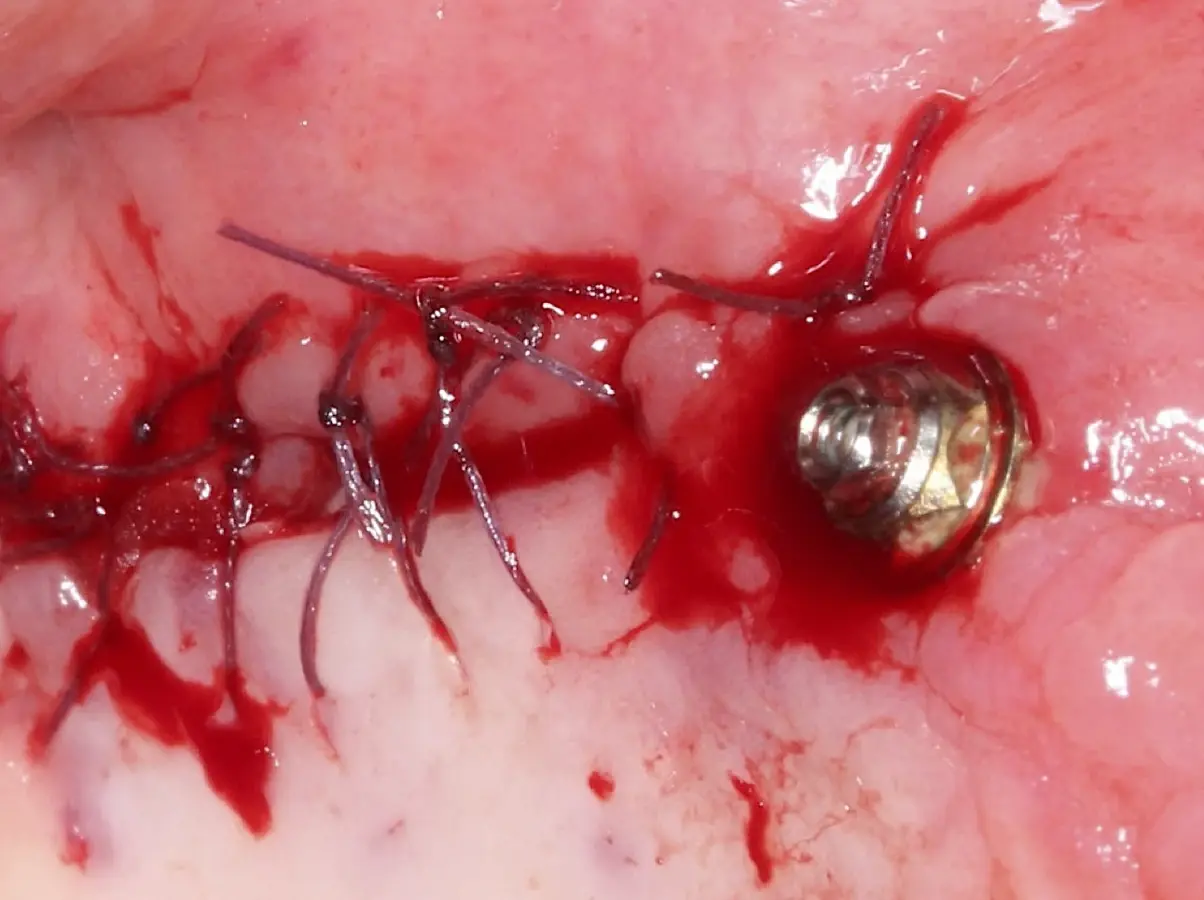

Figura 13. Reposicionamiento del colgajo y sutura (a, b).

Figura 22. Afrontamiento de colgajo y sutura.

Figura 30. Liberación del colgajo, afrontamiento sin tensión y sutura.